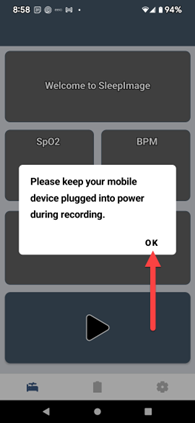

SLEEPIMAGE APP (Android)

SLEEPIMAGE APP (Android)

SLEEPIMAGE APP (Android)

SLEEPIMAGE APP (Android)

SLEEPIMAGE APP (Android)

SLEEPIMAGE APP (Android)

SLEEPIMAGE APP (Android)

SLEEPIMAGE APP (Android)

SLEEPIMAGE APP (Android)

SLEEPIMAGE APP (Android)

SLEEPIMAGE APP (Android)

SLEEPIMAGE APP (Android)

SLEEPIMAGE APP (Android)

SLEEPIMAGE APP (Android)

SLEEPIMAGE APP (Android)

SLEEPIMAGE APP (Android)

SLEEPIMAGE APP (Android)

SLEEPIMAGE APP (Android)

SLEEPIMAGE APP (Android)

SLEEPIMAGE APP (Android)

SLEEPIMAGE APP (iPhone)

SLEEPIMAGE APP (Android)

SLEEPIMAGE APP (Android)

SLEEPIMAGE APP (Android)

SLEEPIMAGE APP (Android)

SLEEPIMAGE APP (Android)

SLEEPIMAGE APP (Android)

SLEEPIMAGE APP (Android)

SLEEPIMAGE APP (Android)